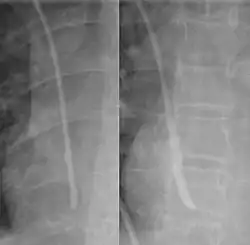

The line is then inserted using the Seldinger technique: a blunt guidewire is passed through the needle, then the needle is removed. A dilating device may be passed over the guidewire to expand the tract. Finally, the central line itself is then passed over the guidewire, which is then removed. All the lumens of the line are aspirated (to ensure that they are all positioned inside the vein) and flushed with either saline or heparin.[1] A chest X-ray may be performed afterwards to confirm that the line is positioned inside the superior vena cava and no pneumothorax was caused inadvertently. On anteroposterior X-rays, a catheter tip between 55 and 29 mm below the level of the carina is regarded as acceptable placement.[37] Electromagnetic tracking can be used to verify tip placement and provide guidance during insertion, obviating the need for the X-ray afterwards.

Chest x-ray with catheter in the right subclavian vein -

During subclavian vein central line placement, the catheter can be accidentally pushed into the internal jugular vein on the same side instead of the superior vena cava. A chest x-ray is performed after insertion to rule out this possibility.[26] The tip of the catheter can also be misdirected into the contralateral (opposite side) subclavian vein in the neck, rather than into the superior vena cava.